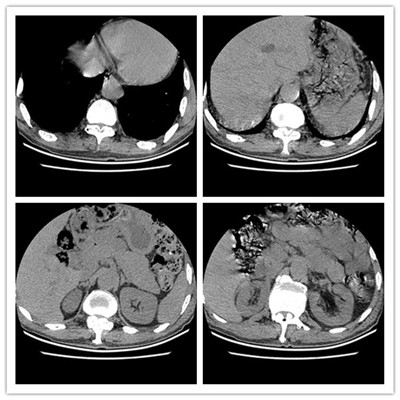

患者张某,男,69余,患者以“腰痛伴双下肢抽痛5年,摔伤后加重伴行走困难6天”在当地诊断为腰椎滑脱伴椎管狭窄(图1),转入我科拟行手术治疗,入院后完善检查,发现患者有广泛严重的胸椎黄韧带骨化伴不全瘫(图2),钙化范围涉及了胸2至腰2节段,且很多节段压迫极其严重(图3),原本相当于大拇指粗细的椎管,被钙化的黄韧带硬生生挤成了一条缝。

图2 胸椎

图3

该患者,压迫范围如此广泛,且压缩程度如此严重,实属罕见。且患者在查体时发现双下肢肌力3级左右,双侧肌张力明显升高,踝阵挛阳性,患者活动时双下肢有难以自控的抽动,无法自行下地行走。

入院后经科室集体讨论,反复研究,压迫如此广泛严重,术中稍有不慎,即有可能致患者瘫痪,手术风险极大。与患者家属充分沟通后,高宗强副主任医师最终决定为患者施行后路长节段胸椎椎板减压并钉棒内固定术。先给医院上报重大手术,在11月20日晨9时许,兰宾尚主任、张纯主任现场把关,王芳术中电生理监测,李有才教授、何家璇进行全麻,由高宗强副主任医师主刀,刘若西博士、刘鹏飞规培医师协助下于在全麻下行后路减压钉棒内固定术(从胸10/11-腰1/2节段),术中发现脊髓压迫极其严重,且骨化块异常坚硬,钙化的黄韧带将硬膜囊紧紧卡死并紧密粘连,术中邀请神外王睿智副主任医师修补硬膜囊,手术持续约8小时,于下午5时许顺利结束。现患者神经功能恢复良好,术前明显增高的肌张力恢复正常,踝阵挛消失(图4),难以自控的抽动消失。